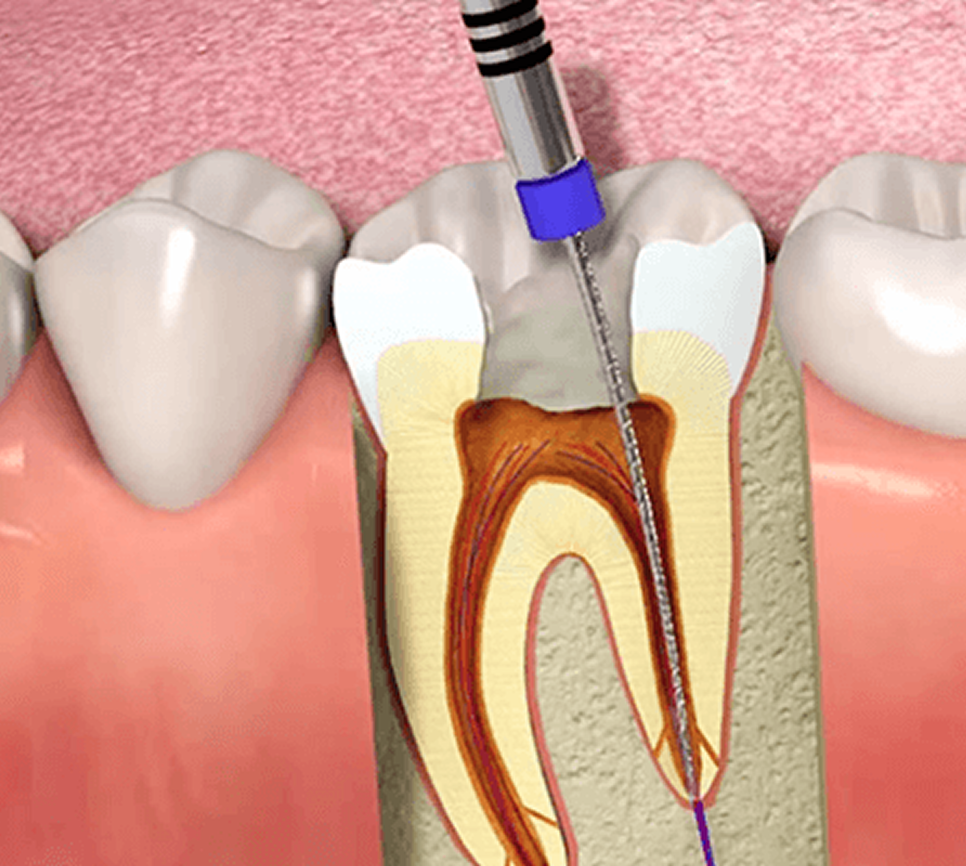

Implant & Restorative Dentistry

From preventive care to advanced dental treatments, we provide comprehensive solutions tailored for children, adults, and seniors.

From general and preventive dentistry to cosmetic, orthodontic, and advanced restorative treatments, we offer comprehensive dental solutions for patients of all age groups.